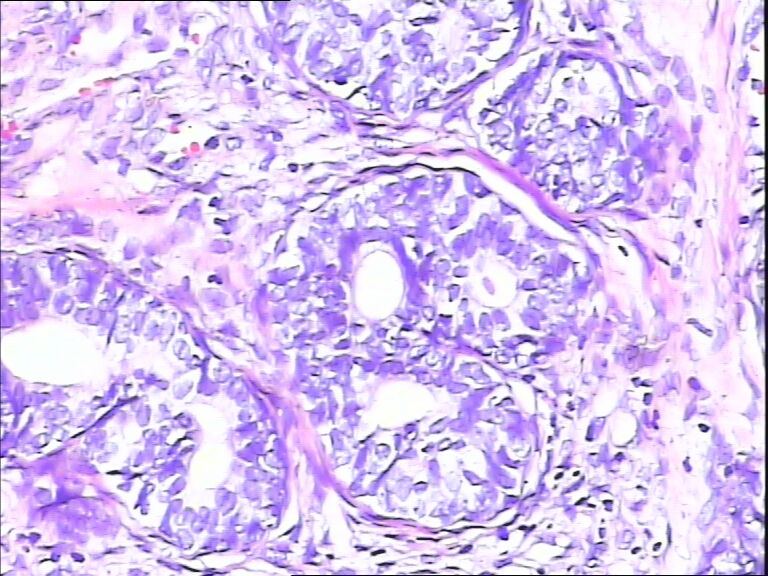

前列腺,请教,急!

前列腺够癌吗?